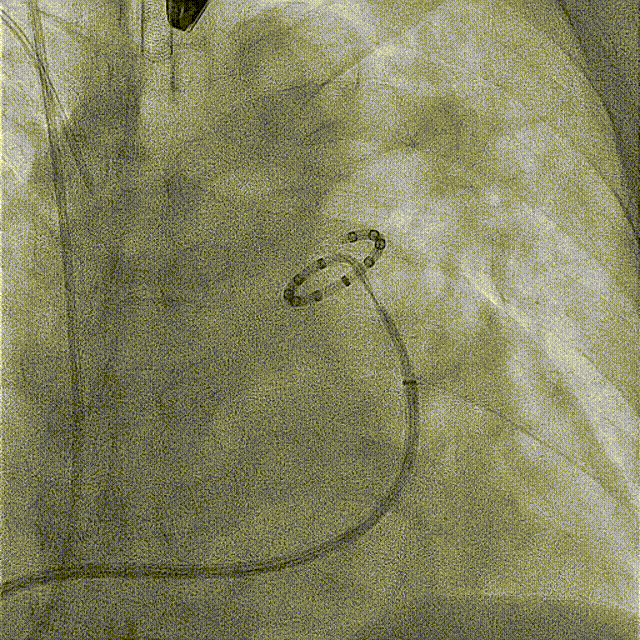

PADN术中造影和导管消融图(见下图):

LAO0°+CRA20°工作体位依次进行A、B、C点消融